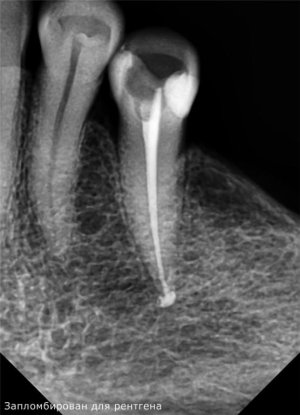

Здравствуйте! 21 апреля мне запломбировали каналы.Сутки зуб не болел,а вчера началась боль острая при надавливании.

Прошу специалистов внимательно разглядеть снимки.Мне кажется каналы,в корне не достаточно плотно запломбированы материалом и часть выходит за пределы корня.

Я делала через фотошоп контраст и увидела не заполненные места.